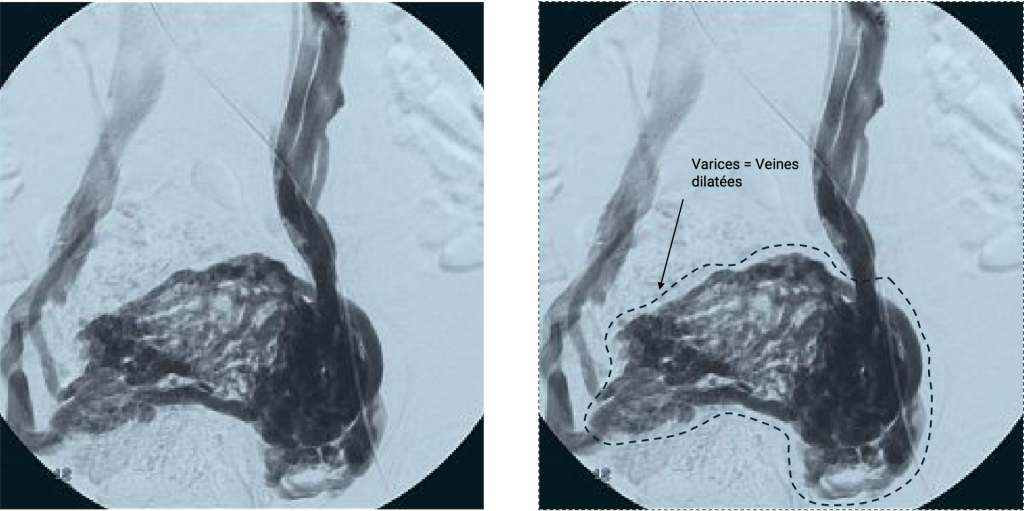

Quels examens permettent de diagnostiquer des varices pelviennes ?

Différents examens permettent de faire le diagnostic de varices pelviennes et d’exclure d’autres pathologies comme les fibromes ou l’adénomyose

Phlébographie pelvienne : examen radiologique invasif, réalisé surtout en vue d’un traitement (embolisation).